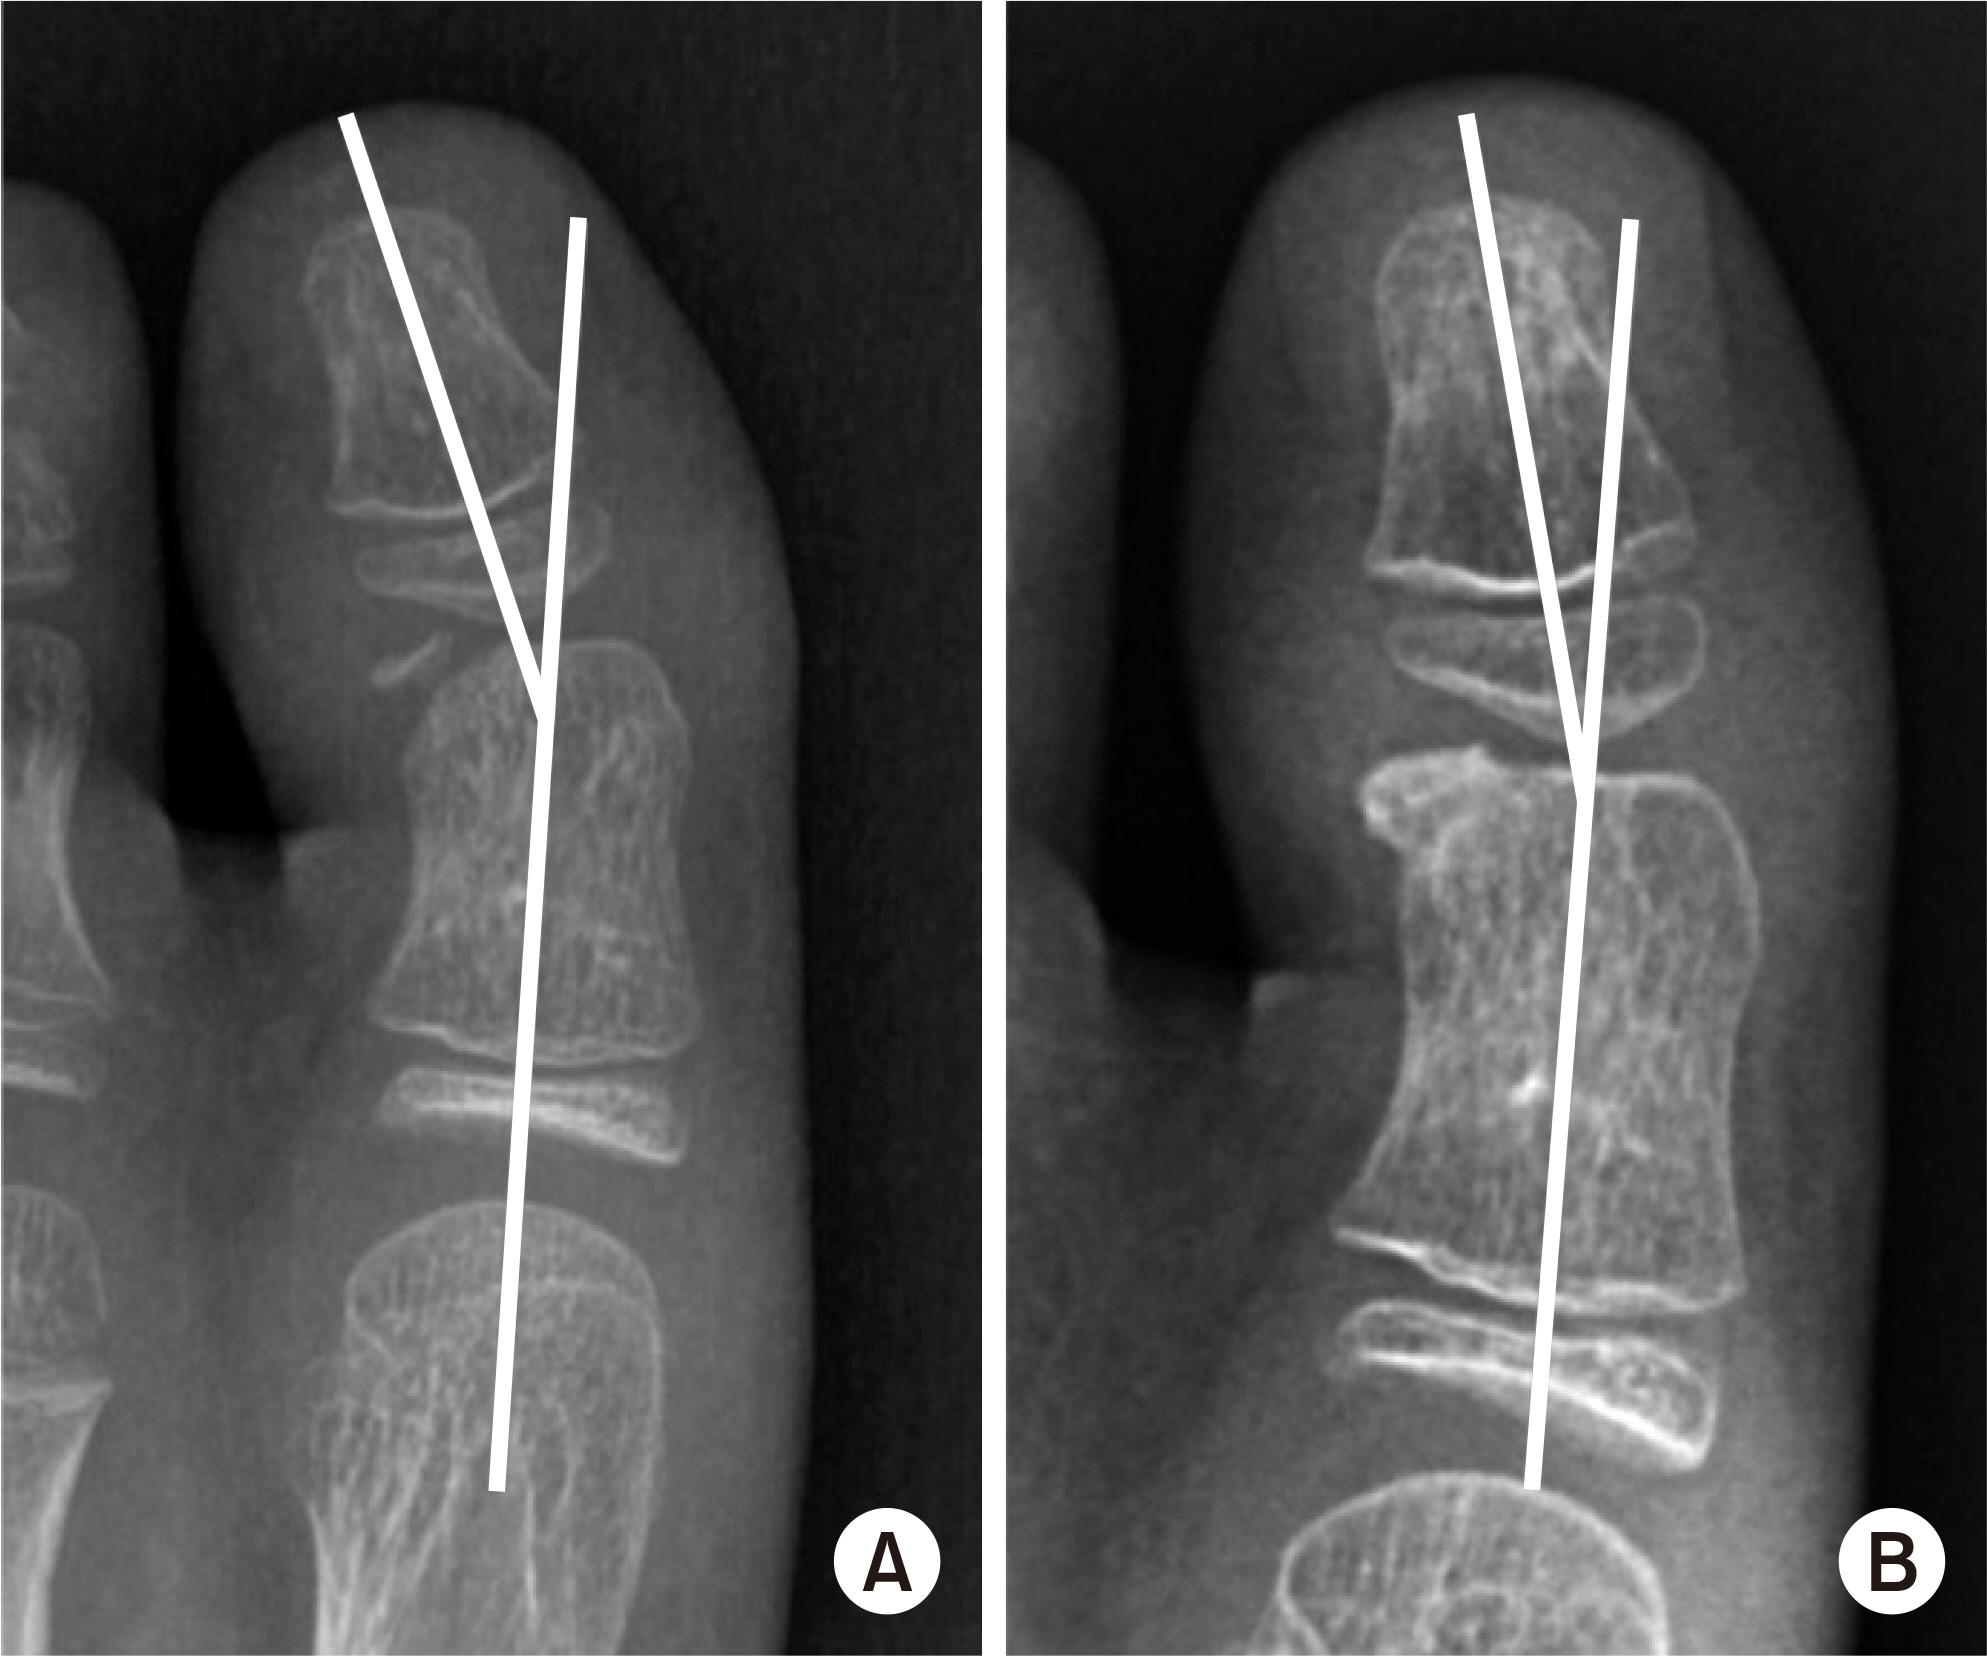

Fig. 1.

Measurement of the hallux valgus interphalangeus (HVIP) angle.